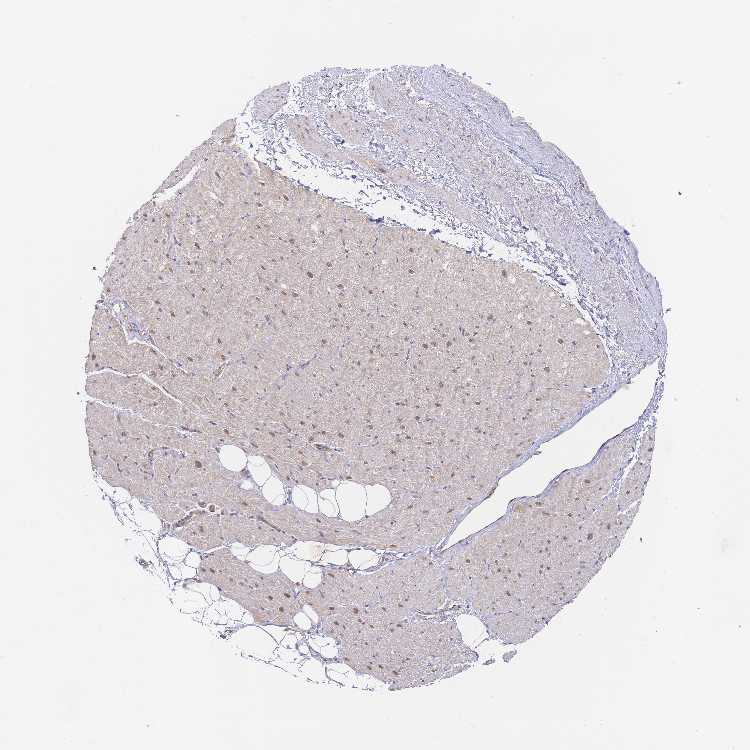

HEART MUSCLE - Antibody stainingi

Antibody staining in the annotated cell types in the current human tissue is reported as not detected, low, medium, or high, based on conventional immunohistochemistry profiling in selected tissues. This score is based on the combination of the staining intensity and fraction of stained cells.

Each image is clickable and will lead to virtual microscopy that enables deeper exploration of all samples and also displays staining intensity scores, fraction scores and subcellular localization as well as patient and tissue information for each sample.

Antibody HPA061638Antibody CAB022345

Cardiomyocytes MediumMedium